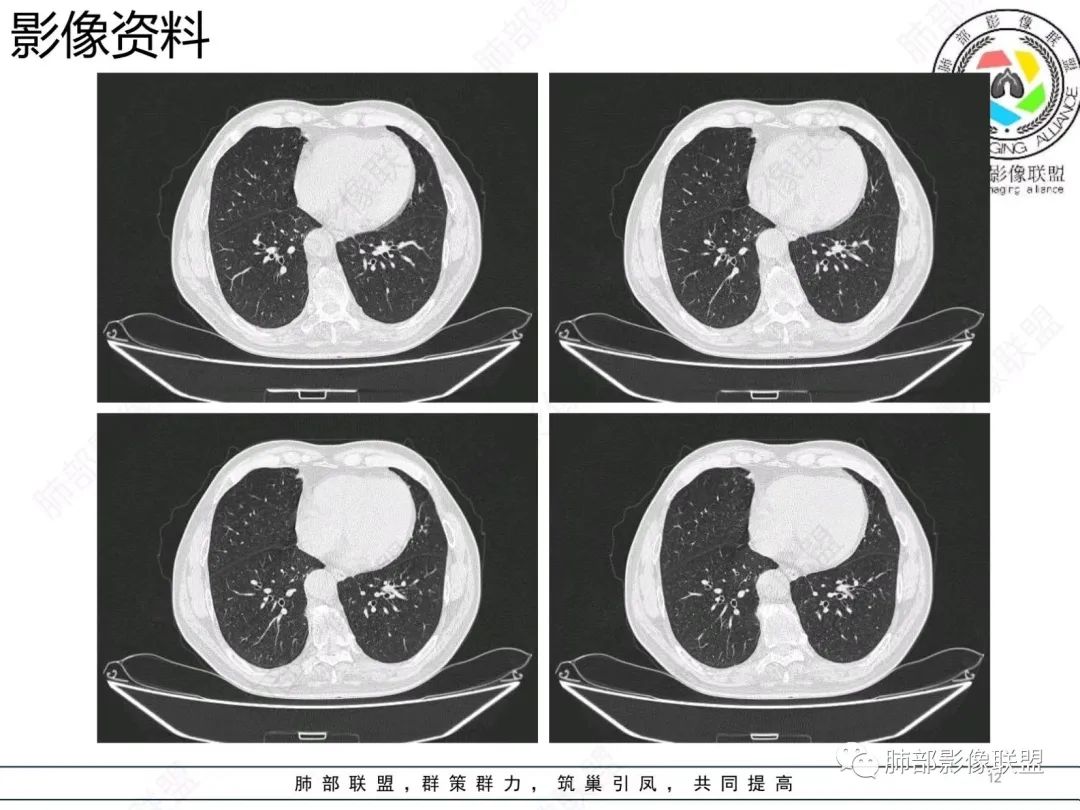

粘液腺癌CT表现:

1.结节型肺粘液腺癌以中老年女性多见,单发,发病部位常位于两下肺胸膜下(肺外周带)。

2.多数病灶具备典型恶性肿瘤征象,但是不典型者仍不少见。可有分叶和棘状突起,但较少出现典型毛刺征。强化程度不如一般的腺癌病灶那么显著。

3.病灶常呈圆形或不规则形,实性结节略多于混合磨玻璃结节,少见于纯磨玻璃结节;或囊实性结节影或肿块,密度混杂,部分可出现钙化;病灶边界可清楚,也可模糊,须与炎性结节鉴别;周围可有类圆形磨玻璃密度卫星灶;表现为实性结节病灶,收缩力可能表现不明显,较少胸膜凹陷或血管集聚,须与良性结节鉴别。

4.原发性肺粘液腺癌侵袭力相对较低,发展慢;病灶较少破坏支气管及血管,可表现为血管造影征及空气支气管征。较少胸膜侵犯,也较少肺门纵隔淋巴结转移。

病理影像:

1.病理基础:肺原发性粘液腺癌的肿瘤细胞产生大量粘液,聚集于细胞内,破入细胞间隙甚至肺泡、末梢细支气管,致使病灶密度增高呈混合磨玻璃或实性结节。

2.粘液的直接扩散和漂移,致使病灶边界模糊和病灶呈多灶性生长。

3.粘液的重力效应致使病灶常位于胸膜下或叶间胸膜附近。

4.病灶内气管、血管破坏不明显,可出现血管造影征及空气支气管征;也提示病灶侵袭力较低。

5.粘液的张力(占位效应)常可抵消病灶收缩力,致使病灶收缩力表现常较弱。